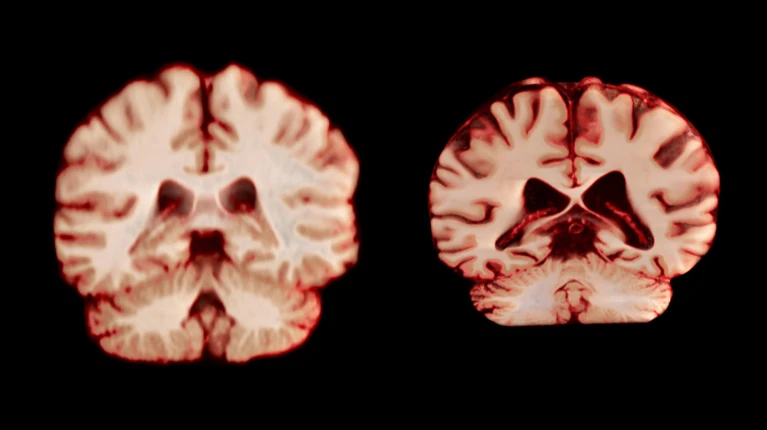

衰老過程中男性大腦萎縮速度快于女性